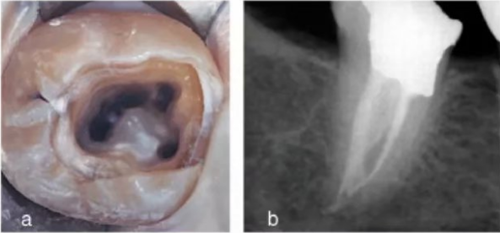

使用牙周探針對(duì)牙冠或牙頸部形態(tài)進(jìn)行臨床檢查有助于發(fā)現(xiàn)額外的牙根。一個(gè)額外的牙尖(副磨牙結(jié)節(jié),tuberculum paramolare)或明顯突出的遠(yuǎn)頰或遠(yuǎn)舌小葉,伴有頸部的突出,可能表明存在額外的牙根。遠(yuǎn)舌根的根管口位于主要的遠(yuǎn)中根管的近舌側(cè),因此開髓洞型需要預(yù)備成矩形或梯形。使用牙髓探針仔細(xì)檢查髓室底的暗色的發(fā)育溝,可以精確的定位遠(yuǎn)舌根根管口。

使用手術(shù)顯微鏡是非常有幫助的,特別是在那些根管口被鈣化物覆蓋的病例中,這些鈣化物可以使用超聲尖或長(zhǎng)柄小球鉆輕松去除(圖 14a-d)。